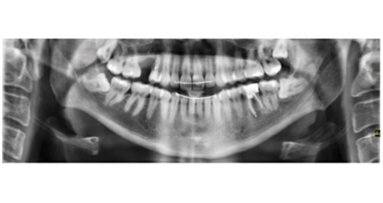

Los cementos quirúrgicos (CQ) se comenzaron a utilizar en 1923, y hoy en día se usan extensamente en cirugía y periodoncia para cubrir y proteger lechos quirúrgicos. Su utilización abarca desde cirugías de tejido conjuntivo hasta una gingivoplastía o tratamientos periodontales no quirúrgicos. Existe cierta controversia sobre la utilidad del cemento quirúrgico en la cirugía periodontal, específicamete sobre si su utilización realmente acelera el proceso de regeneración de los tejidos periodontales o no1.

Los CQ se han utilizado a través del tiempo para prevenir infecciones postoperatorias y para acelerar la regeneración tisular. La culminación de las etapas de la sanación de las heridas termina en volver a su estructura normal y en nueva formación de tejido4. El objetivo principal de cualquier cirugía oral es el restablecimiento de los tejidos a su estado fisiológico, aunque hay que tener en cuenta que no siempre puede llegarse a un 100%, sino a una aproximación, dependiendo de las condiciones del paciente y de su cooperación con los tratamientos ejecutados.

El CQ fue evaluado luego de la realización de alargamiento de corona en 36 pacientes, y se halló recesión gingival en el 57.8% del grupo control (a los que no se les aplicó el cemento quirúrgico) y solo un 5.5% a los que sí6.

El uso de CQ en los tratamientos periodontales no quirúrgicos es beneficioso, ya que retiene el coágulo y previene infecciones futuras7. Utilizar CQ en tratamientos no solo quirúrgicos periodontales, sino también no quirúrgicos, como raspado y alisado radicular, es eficaz al eliminarlo después de 7-8 días8,9.

La utilización de HemCon Dental Dressing (HDD) o cementos hemostáticos quirúrgicos, realmente mejora bastante el sangramiento en las cirugías orales y acelera la sanación de los tejidos en comparación a los lechos que no reciben estos cementos10. A pesar de que hoy en día el uso de cementos quirúrgicos es controvertido, existe evidencia científica positiva para su utilización, aunque sería de gran beneficio que se realizaran más estudios clínicos que evaluasen las propiedades de los diferentes tipos de cementos, incluyendo la proliferación bacteriana sobre éstos.